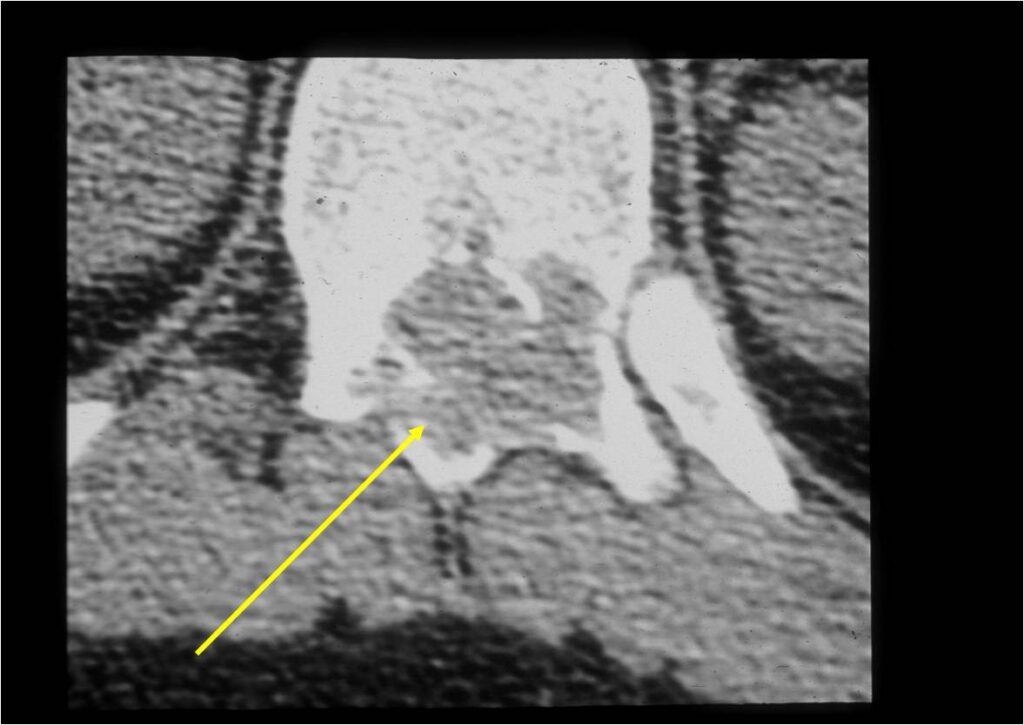

CT Scan:

- More useful for detecting mineralization and evaluating extent of bone destruction than plain X-ray

- The periosteum remains intact around the soft tissue component. Might need a CT scan to detect the subtle calcification (Egg Shell Rim of Calcification) associated with an intact periosteal reaction

- The lesion may be entirely radiolucent but usually shows some degree of mineralization. Mineralization may appear stippled like cartilage but do not see chondroid pathologically. Mineralization is sometimes better detected on a CT scan rather than an x-ray.

- Soft tissue component usually surrounded by shell of reactive bone or periosteum (Egg Shell Rim of Calcification)